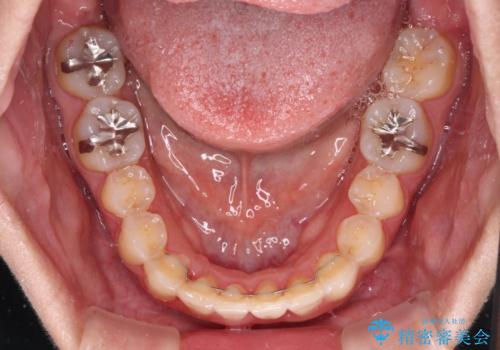

前歯のデコボコをインビザラインでスッキリと

- 上下前歯のデコボコを気にして来院された患者様です。

デコボコを解消する過程で、歯列の拡大により口元が突出する可能性があったため、4本の親知らずを抜歯しておき、歯列全体が後方に移動するように設計し、インビザラインにて矯正治療を行うこととしました。

日々の装着時間をしっかりと守って治療の臨んでくださったため、治療前のシミュレーションに近い形で矯正治療を進めて行くことができました。